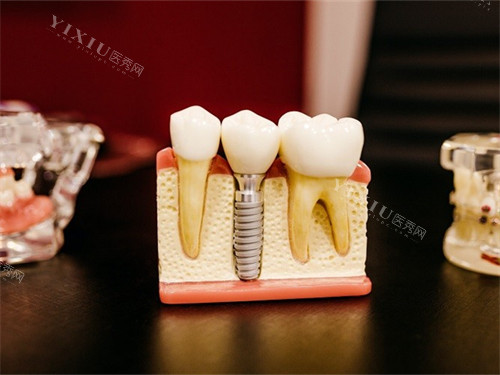

数字种植牙通过CBCT扫描、口内光学扫描获取三维口腔数据,生成虚拟模型后进行术前规划,并利用3D打印导板引导种植体植入。传统种植牙则依赖医生经验,通过物理模型和X光片判断种植位置,依赖手工操作完成植入。

通过石膏模型和X光片评估口腔状况,依赖医生对解剖结构的理解。

手工操作:

医生通过切开牙龈、翻瓣、缝合等步骤完成种植,对医生经验要求较高。